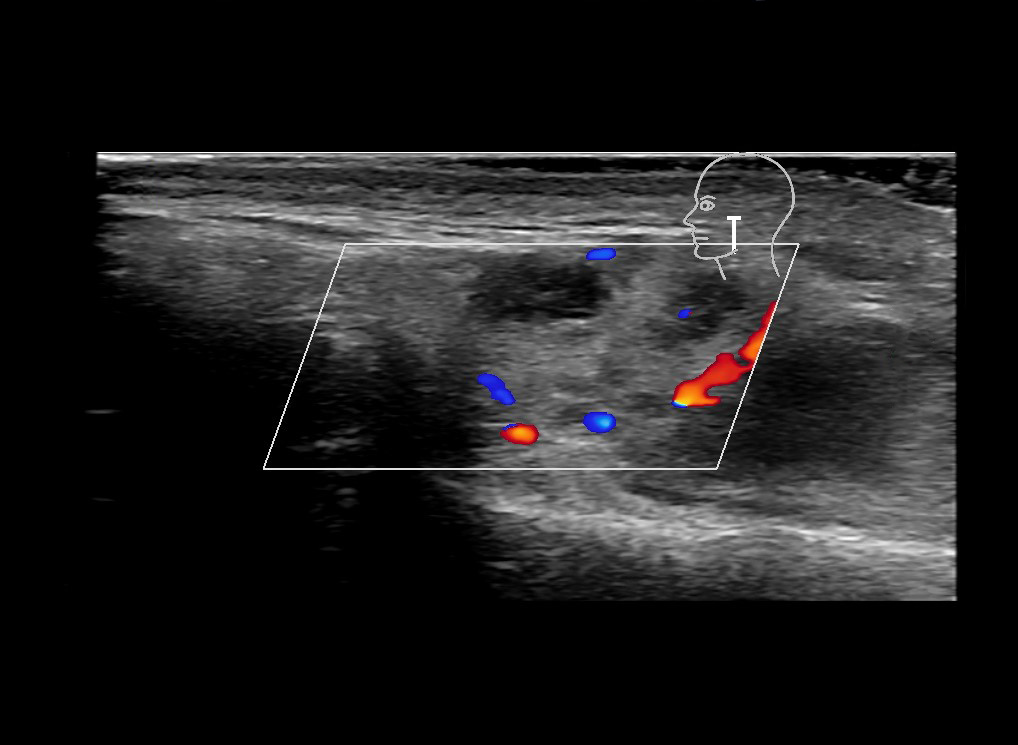

With ultrasound signs of inflammation can be visualized. Edema can be seen as a hyperechoic appearance of the subcutaneous fat, sometimes separated by hypoechoic fluid filled area’s, known as cobblestone appearance. Increased vascularization (hypervascularity) can be seen on colour Doppler. An abscess will appear as a fluid collection appearing as an irregular hypoechoic area with heterogeneous internal echoes and a thickened wall. Posterior acoustic enhancement can be present, and there is vascularity around but not within the mass. Under ultrasound guidance, abscesses can be managed by needle aspirations (18G) under antibiotic cover.

Study the first image to recognize the different layers. If you are sure about the layers, swipe to the second image to view the answer (if applicable).

Hover over an image to view the secondary image or click on the image title for more information.